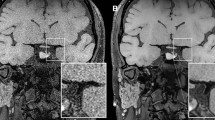

Between 2011 to 2018, thirty-one patients (28 males [90.3%], 3 females [9.7%]; mean age 62.2 ± 13.9 [16–85] years old) with severe symptomatic VBS, who had PTAS, were enrolled in this study (Table 1, supplementary information). All patients received medical treatment on presentation of symptoms including impaired consciousness due to cerebral ischemia in the vertebrobasilar territory. Clinical and MR findings1 were used to identify the etiology of the vascular stenosis as either atherosclerosis, dissection, or dissection in atherosclerosis (DA)8. Dissection was diagnosed by clinical history of traumatic events (such as massage) or headache and MR findings of intramural hematoma. DA was diagnosed by the presence of dissection in an atherosclerotic segment of an artery (Fig. 1). Besides having clinical findings of atherosclerosis and dissection, patients with DA can present with intimal dissection on angiography, or calcified plaques on CT or MRI, or both. Atherosclerosis-related risk factors were also recorded. The indications for PTAS in our cases of VBS were: 1) more than 70% arterial stenosis on imaging study; 2) medically refractory neurological symptoms, including rapidly deteriorated consciousness level. PTAS was performed on an urgent basis when neurological symptoms were recurrent and rapidly becoming more severe.

Hard lesion in a patient with dissection in atherosclerosis (DA). A 54-year-old man was a heavy smoker and had a history of neck massage. He suffered from stroke with right hemiparesis in the past 1 year and had recurrent acute diplopia and dysarthria 1 month ago. Left vertebral angiogram showed a 90% stenotic lesion of the left distal vertebral artery (a, arrowhead) and disrupted intimal flaps (a, arrow). VW-MRI showed low signal intensity on fat-suppressed T1WI (b, arrow) and T2WI (c, arrow) and strong enhancement on contrast-enhanced fat-suppressed T1WI (d, arrow). PTAS was done and revealed a predilatation pressure (PP) of 6.5 atm. A 4 × 20 mm Wingspan stent was deployed in the left distal vertebral artery to basilar artery (e). About 30% residual stenosis was noted on the control angiogram (e, arrow). A 2-year follow-up CTA, curved multi-planar reconstruction, revealed 90% in-stent restenosis (f, arrow) and 30% residual stenosis of the proximal stent (f, arrowhead).